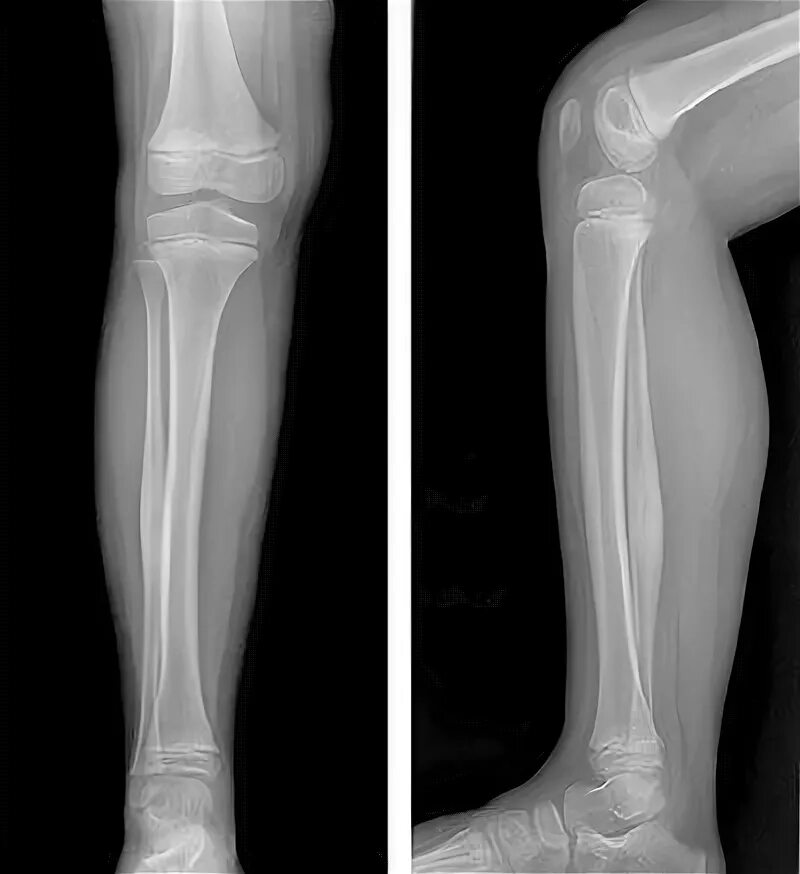

Трещина в кости ноги сколько